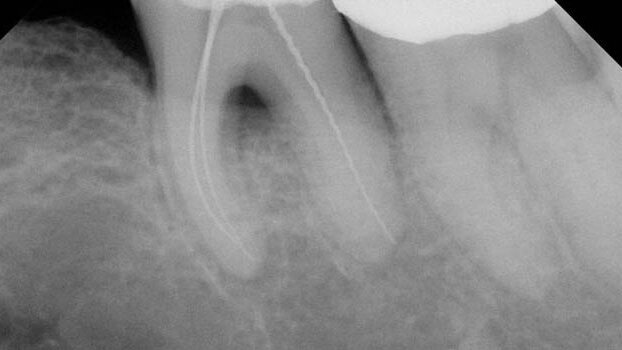

By this time, canals may be transported, blocked or ledged (Figure 1). Yet these are the instruments recommended for glide path creation. It is important to emphasize K-file difficulties don’t start with a 25. Depending upon the canal they are negotiating blockage, ledging or transportation occurs before the canal is instrumented to a 20. Given this situation, the continued use of K-files to shape the canal prior to the use of rotary NiTi is an endodontic absurdity.